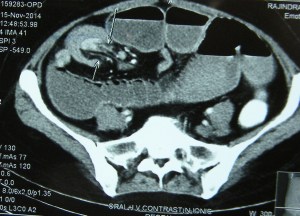

20.11.14 An adult intussusception, diagnosed on US and CT, in a 50-years old female, presenting with sub-acute intestinal obstruction of many weeks, was treated by resection of the segment of distal ileum bearing the intussusception. On cut section, it was found to contain a big pedunculated benign-looking tumour arising from the ileum.